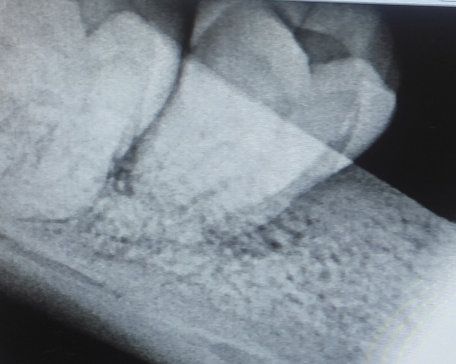

У меня зуб болит. Я его лечила 3 года назад. Мне поставили штифт в декабре 2015, он опять заболел, сделали снимок, оказалось, что он был плохо пролечен. Сняли пломбу, смогли пройти только один канал, во втором канале материал, третий мне врач не смог пройти (инструмент упирался в десну). Тогда еще врач сказал, что этот зуб только удалять, я не согласилась на удаление и мне его просто перекрыли пломбой, теперь опять побаливает.

Как думаете, нужно удалять или его еще можно спасти?

В зубе имеется перфорация, к сожалению, такой зуб спасти и сохранить невозможно.